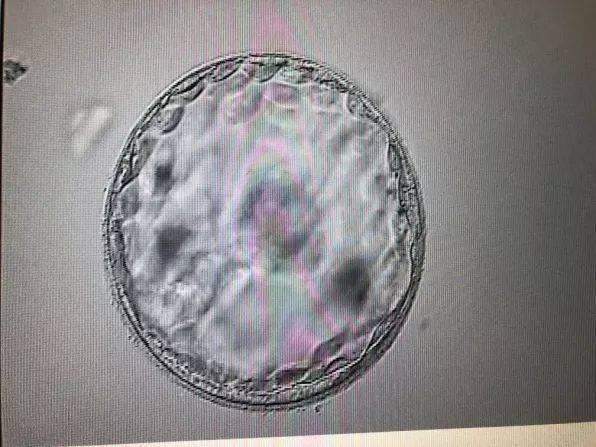

移植囊胚是指将体外受精后的胚胎培养至第5天,形成囊胚阶段后,将其移植到母体子宫内。相较于胚胎移植,囊胚移植的成功率更高,且胚胎在子宫内发育的时间更长,有利于提高妊娠率。